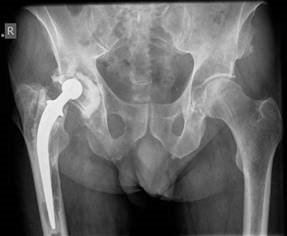

Structured Hip Oral Examination Question 2 EXAMINER : This is an anteroposterior (AP) radiograph of a 52-year…